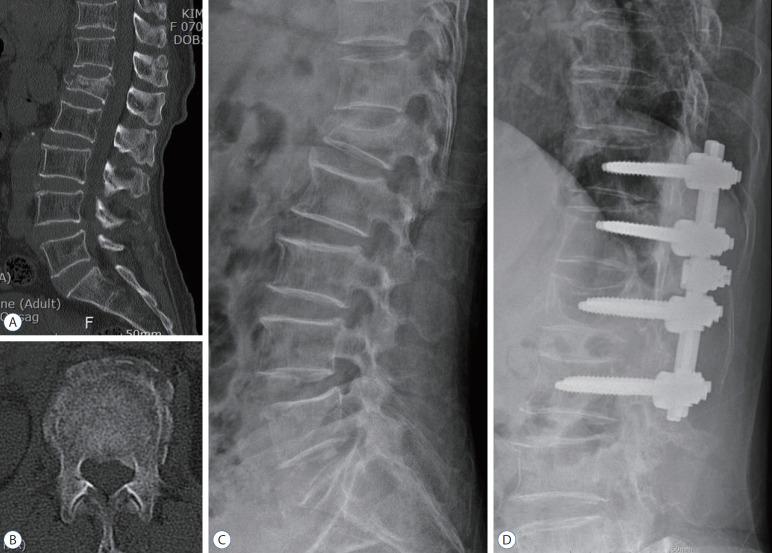

This retrospective study enrolled 35 female patients with mean age of 73.77±6.71 years (61-88) diagnosed as osteoporotic TL burst fracture with ≥4 of thoracolumbar injury classification and severity (TLICS) score and no neurological deficits. All patients were treated by teriparatide only (12 of group A), teriparatide plus vertebroplasty (12 of group B), or surgical fixation with fusion (11 of group C), and followed up for 12 months. Radiological outcomes were evaluated using radiological parameters including kyphotic angle (KA), segmental vertebral kyphotic angle (SVKA), compression ratio (CR), and vertebral body height (anterior [AH], middle [MH], posterior [PH]). Functional outcomes were evaluated using visual analog scale (VAS) and Macnab classification (MC).

There were no statistical significant differences in age, bone mineral density (-3.36±0.73), and TLICS score (4.34±0.48) among the three groups (p>0.05). Teriparatide was administered during 8.63±2.32 months in group A and B. In 12-month radiological outcomes, there were significant restoration in SVKA, CR, AH, and MH of group B and KA, SVKA, CR, AH, and MH of group C compared to group A with no radiological changes (p<0.05). All groups showed similar significant improvements in 12-month functional outcomes, although group B and C showed a better 1-month VAS, 1-month MC, 3-month MC compared to group A (p<0.05).

Non-surgical treatment with teriparatide showed similar 12-month functional outcomes compared to surgical fixation with fusion. The additional vertebroplasty to teriparatide and surgical fixation with fusion were more helpful to improve short-term functional outcomes with structural restoration compared to teriparatide only.